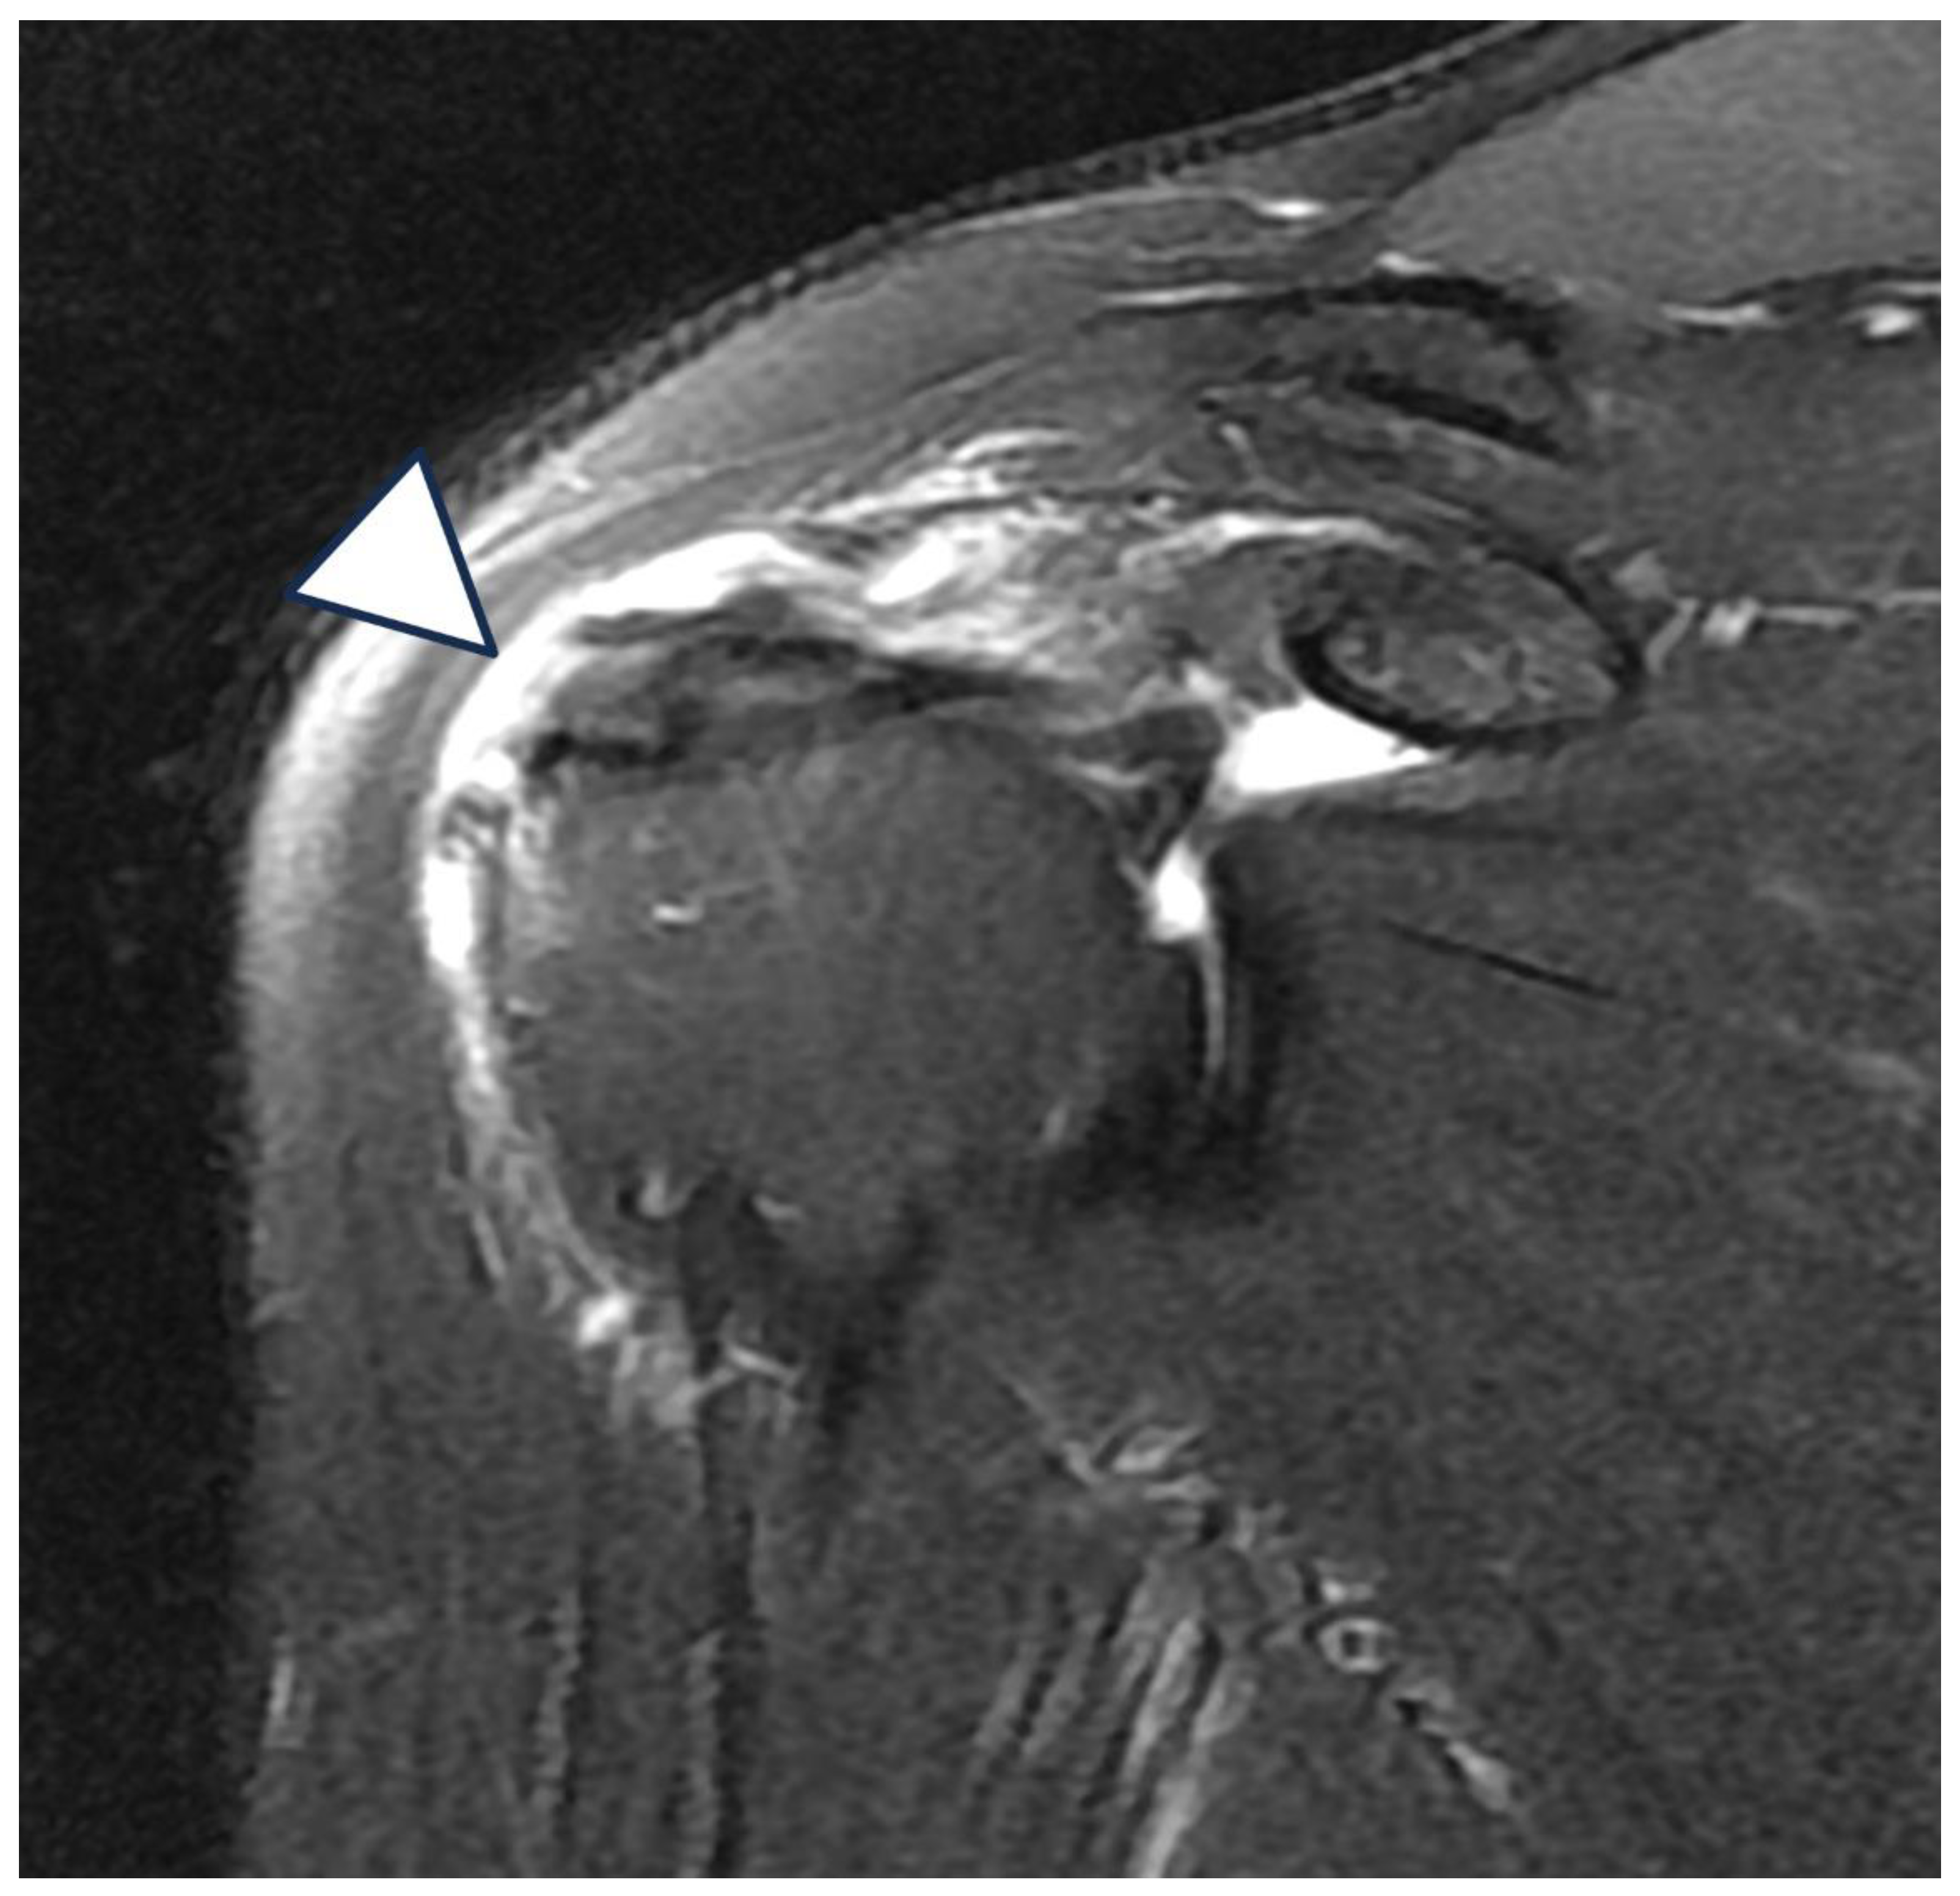

Figure 2. (A) Bursal side partial thickness supraspinatus tear with subacromial spur was observed on the preoperative magnetic resonance imaging. (B) Bio-inductive collagen implant located on the tendon is observed in a post-operative magnetic resonance image. (C) A magnetic resonance image 6 months after surgery showed that the bio-inductive collagen implant was absorbed and the bursal side partial tear was fully recovered.

Radiologic assessments using MRI and ultrasonography revealed no evidence of graft failure or retear at any postoperative stage. Serial images demonstrated continuous tendon remodeling and integration of the Bioinductive Collagen Implant into the native rotator cuff tissue. At both 6 and 12 months postoperatively, all patients showed well-incorporated grafts with no signs of structural compromise.